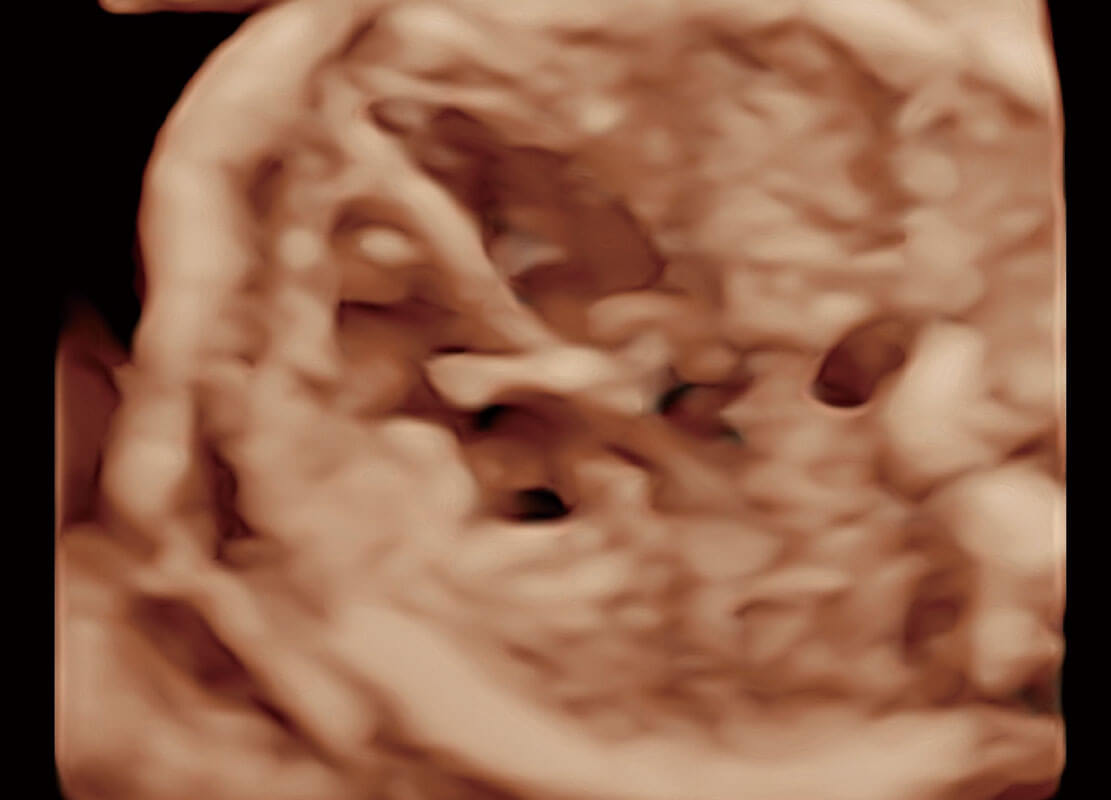

生殖健康

P60优异的图像质量搭载专科探头,在妇科基础疾病的诊断、卵泡生长的监测、输卵管通畅情况的判别等方面为您提供生殖应用方案。

• 腔内三维-宫内节育器

• 腔内三维-光影成像